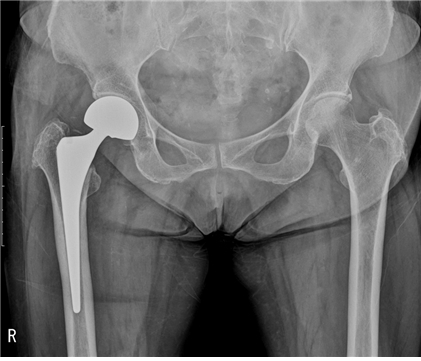

고관절 골절이 발생하면 연령에 관계없이 대부분 수술이 필요합니다. 수술방법은 골절부 고정술, 인공관절 치환술 이렇게 2가지 방법이 있으며 환자가 빨리 움직여야 상태가 좋아지지만 노인들의 경우네는 빨리 움직이기 힘들기 때문에 욕창, 폐렴과 같은 골절로 인한 합병증이 생겨 사망하는 경우가 있습니다.